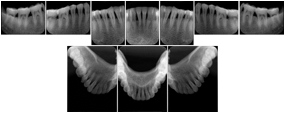

1. A patient in rural Canada visits a general ophthalmologist and is found to have diabetic macular edema. The general ophthalmologist would like to discuss the case with a retina specialist before performing laser surgery. A fluorescein angiogram is done with multiple retinal images taken in a timed series after an intravenous injection. The images along with a Structured Display are shared via a Health Information Exchange with a retina specialist in Calgary, who opens them using his Ophthalmology EMR software and consults via phone with the general ophthalmologist. Both physicians view the images in the same layout so the retina specialist can provide accurate guidance for treating the patient.

2. A patient in rural Iowa visits his primary care physician for management of diabetes. Three non-mydriatic (patient's eyes are not dilated) photographs are taken of the back of each eye, and forwarded electronically along with a Structured Display to an ophthalmologist in Iowa City. The ophthalmologist reads the photos in an agreed upon layout so there is no mistake about what portion of which eye is being viewed. The ophthalmologist is able to tell the primary care physician that his patient does not need to come to Iowa City for face to face ophthalmologic care, but that there is a particular view of the left eye that should be photographed again in 6 months.

Ophthalmic Retinal Study Structured Display

Figure OO-3. Ophthalmic Retinal Study Structured Display